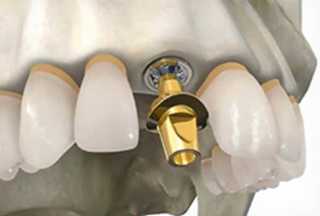

5 Этап. Установка абатмента

![]() |

Абатмент — соединительное звено между имплантом и коронкой. Перед фиксацией абатмента, предварительно за 2 недели, устанавливается формирователь десны. Установка абатмента занимает несколько минут. Одновременно снимается слепок для изготовления коронки. |